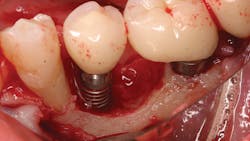

The literature is replete with case reports describing the infection and failure of a dental implant that is adjacent to a tooth with endodontic-induced apical pathology. Unfortunately, periapical lesions can travel to the dental implant and cause an exaggerated loss of attachment in a short period of time (figure 1).7 It is imperative that clinicians expeditiously diagnose and endodontically treat natural teeth with infections adjacent to dental implants.